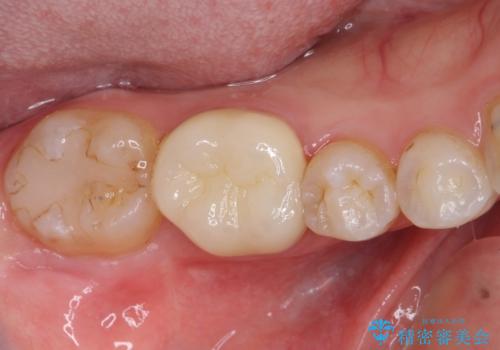

矯正治療後は、奥歯の虫歯や銀歯を補綴・修復治療することとしました。

セラミック治療の注意事項(リスク・副作用など)

- 天然歯を削ります

- 硬い素材は天然歯を傷つけてしまう場合があります

- かみ合わせや歯ぎしりが強すぎる方はセラミックが割れてしまう可能性があります

- 自費診療(保険適用外治療)となります